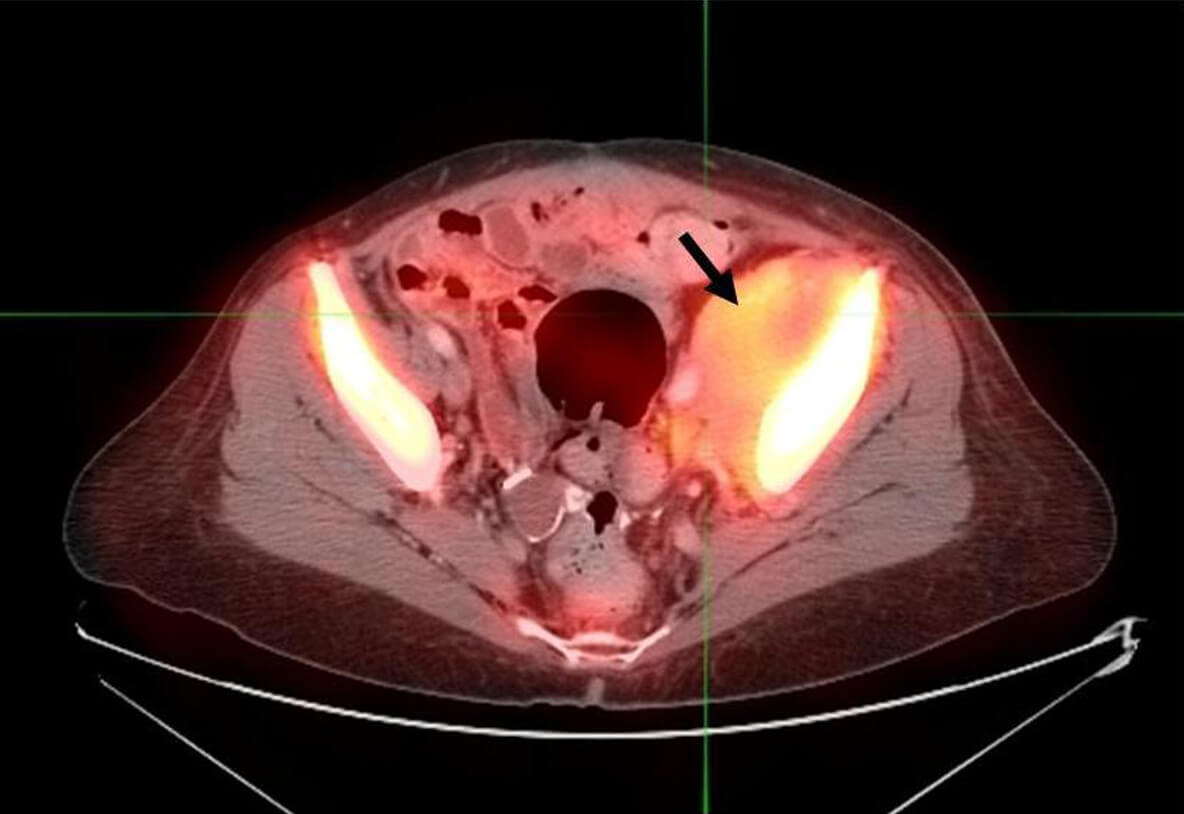

Pelvic ovarian mass

This image, captured by a Tc-EC20 molecular imaging agent, shows a pelvic ovarian mass. The Tc-EC20, under development by Endocyte Inc., may help identify tumors and, in turn, could help in the treatment of advanced ovarian cancer. (Image provided by Endocyte Inc.)

Prior to the start of treatment with EC145, the women were scanned with 99mTc-EC20, a molecular imaging agent that binds to folate receptors (FR) and is being developed by Endocyte as a companion diagnostic tool to identify patients whose tumors express FR, the molecular target for the EC145 therapy. When scanned with EC20, 76 percent of patients were found to be folate-receptor "positive." In the subgroup of patients who were EC20 "positive" and who had failed four or fewer prior therapies, the disease control rate was 75 percent (9 of 12), and two patients exhibited a RECIST partial response. Across all patients, the drug was well tolerated with no grade 4 toxicities. The most common grade 3 toxicity was fatigue (8.2 percent).